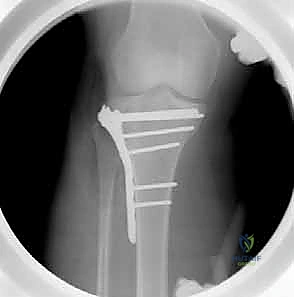

7. التثبيت النهائي بالشرائح والمسامير (Plating)

بعد التأكد من استواء السطح المفصلي بواسطة الأشعة داخل العمليات (C-arm)، يتم تثبيت العظم باستخدام شريحة معدنية تشريحية ذات مسامير مغلقة (Locking Compression Plate - LCP). هذه الشرائح الحديثة تعمل كـ "دعامات داخلية" توفر ثباتاً استثنائياً، وتسمح للمريض ببدء تحريك ركبته في اليوم التالي للجراحة.